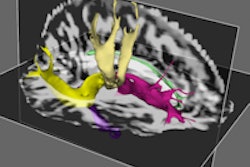

The new Codman Certas Plus programmable valve enables neurosurgeons to preoperatively choose from eight low- to high-pressure settings to control the rate of drainage of cerebrospinal fluid (CSF) from the brain. The valve pressure can be read and adjusted noninvasively or even turned "virtually off" (valve pressure consistently above 400 mm H2O) anytime after implantation using the Codman Certas toolkit, which uses magnetic force to change settings.

The Codman Certas Plus valve is resistant to unintended changes in the valve setting in a 3-tesla MRI scanner and may be integrated with Codman Neuro's Bactiseal antimicrobial catheter and/or Siphonguard antisiphon device, depending on the surgeon's preference.